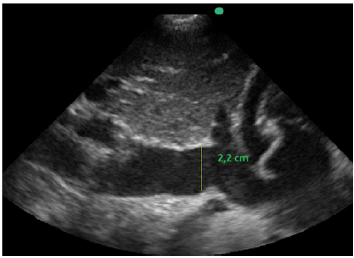

Também foi feita a mensuração da cava na janela subcostal 4 câmaras caval. O seu valor é maior de 2,2 cm e tem variabiliadade menor que 50% aos movimentos respiratórios ainda em ventilação espontânea, conforme a imagem apresentada.